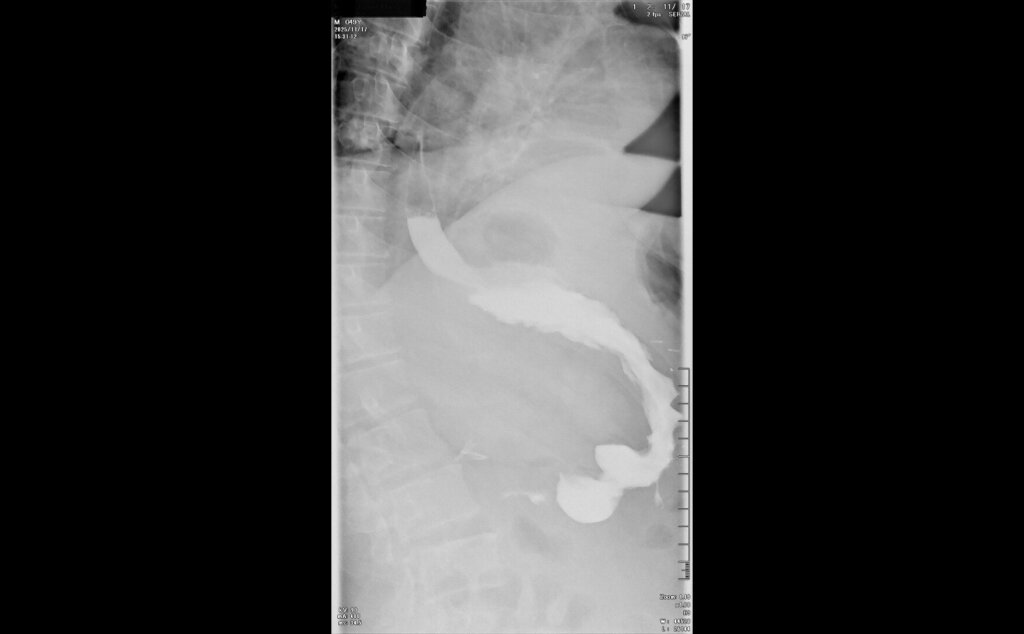

После предварительного обследования произведена операция: ESG + АПК (APC) свода; всего использовано 6 швов, время процедуры ≈ 120 минут.

Под видеоконтролем выполнена эндоскопическая рукавная гастропластика: сшивание стенок желудка при помощи аппарата Overstitch Boston Scientific по длине тела с целью уменьшения объёмов съедаемой пищи.